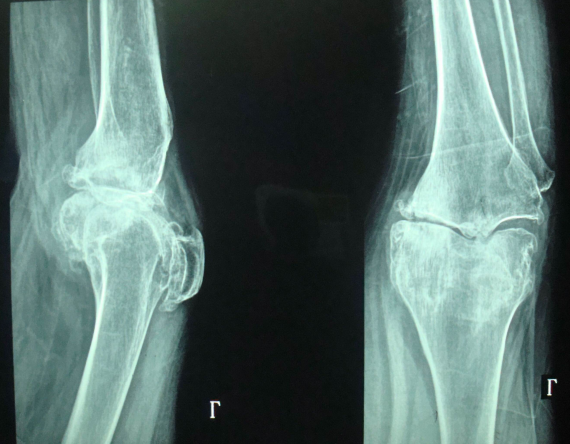

重度骨性關(guān)節(jié)炎術(shù)前X線片